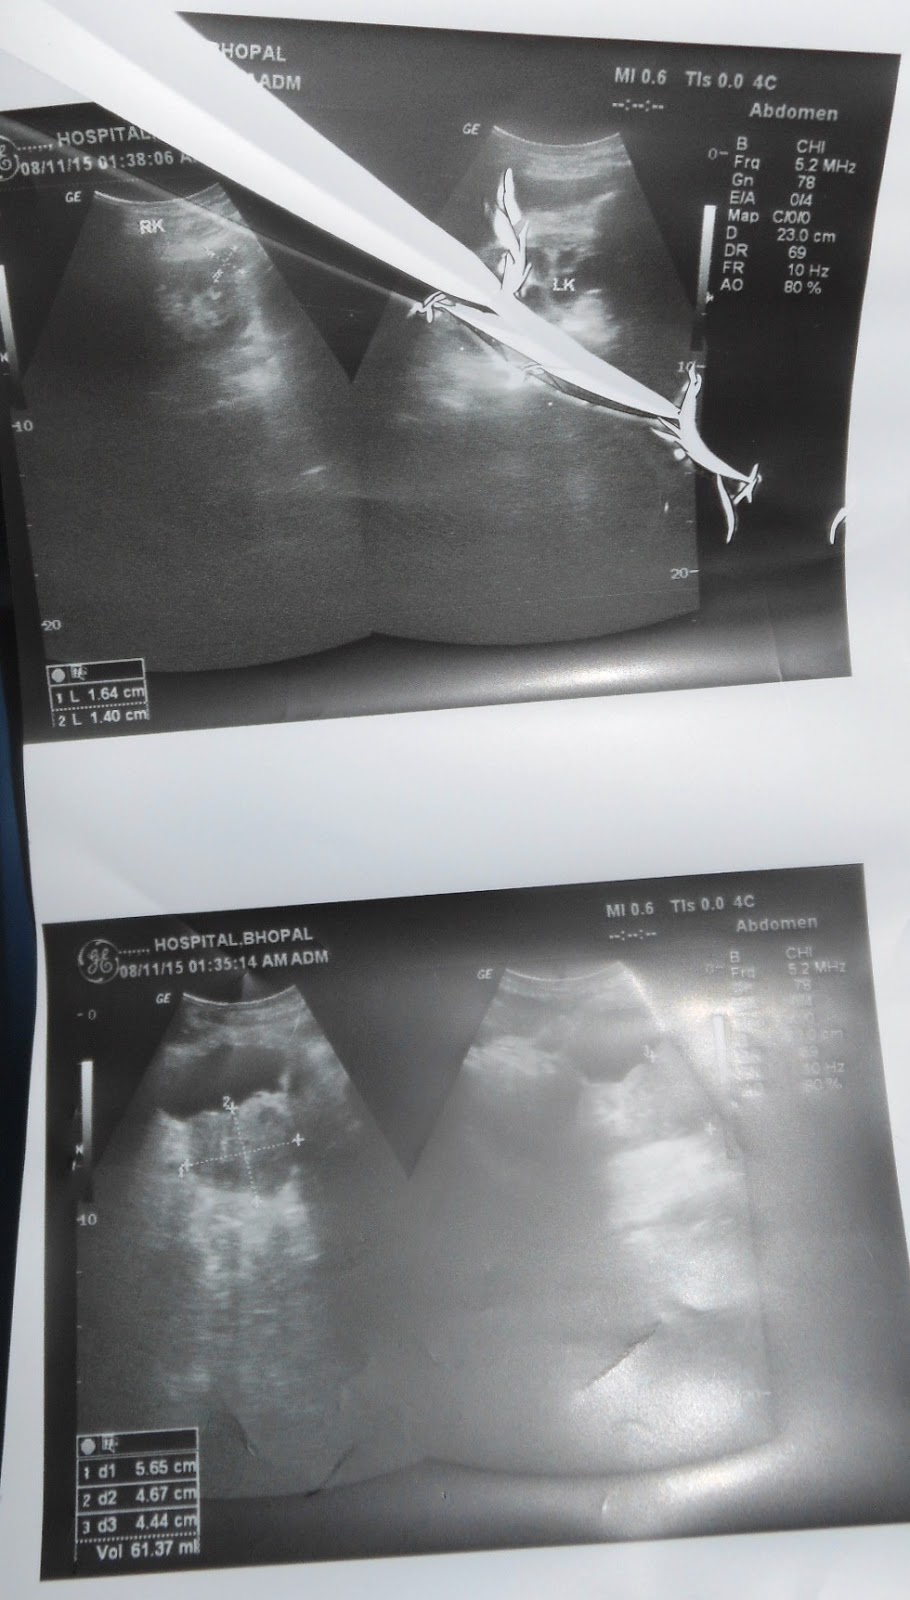

A 99 years old man with gasses distension in abdomen since 7 days

O/E images:

Investigation images: